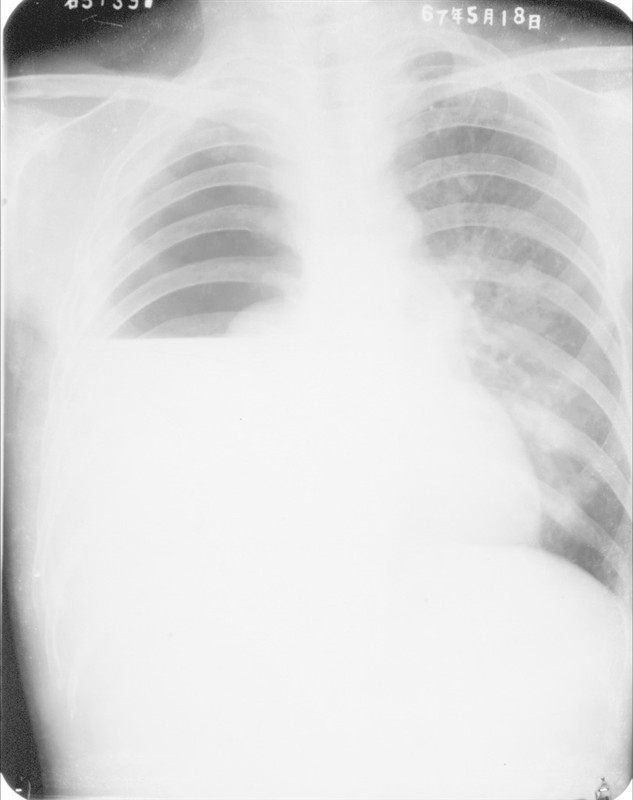

照片名称:液气胸的x射线表现

照片名称:液气胸